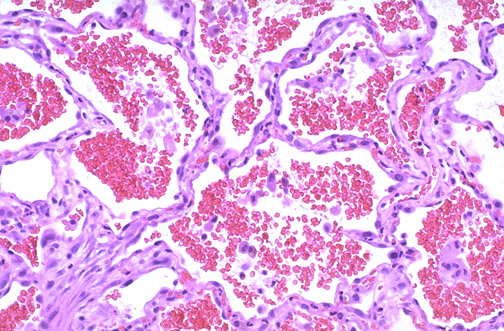

The acute intra-alveolar hemorrhage seen here is a consequence of capillary injury from basement membrane antibody in a patient with Goodpasture syndrome. The glomerular capillaries are targeted as well, leading to a rapidly progressive glomerulonephritis. Circulating anti-glomerular basement membrane antibody can be detected.